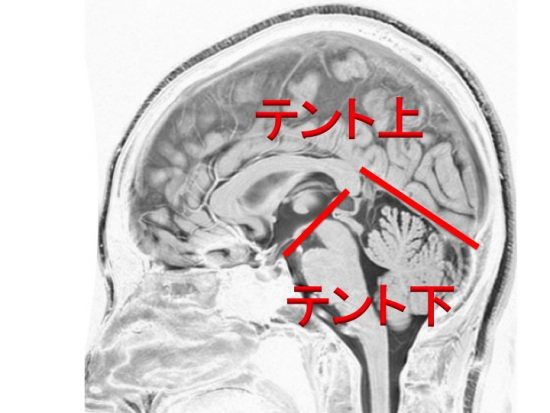

できる場所で治る見込みが違います: テントの上と下でまず区別する

大脳と小脳をわける硬膜をテントといいます

大脳はテント上,小脳と第4脳室はテント下(後頭窩)

1. テント上 上衣腫

2. テント下(後頭窩) 上衣腫

- 上衣腫はテント上(大脳)とテント下(脳幹部周囲)では,手術方法と考え方がぜんぜん違ってきます